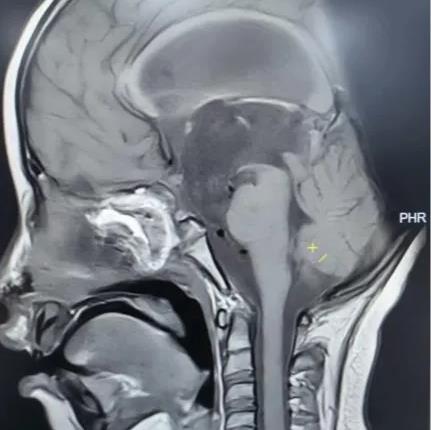

术前核磁共振检查

为精准掌握肿瘤情况,团队为欢欢完善了垂体MRI平扫+增强检查及相关激素水平检测。结果显示:肿瘤体积超过4厘米,形如鸡蛋,已严重压迫视神经与垂体,突入第三脑室,并与周围重要神经血管结构紧密粘连。颅咽管瘤是一种起源于颅底的先天性良性肿瘤,因体积大、位置深,且毗邻下丘脑、视神经、垂体等重要结构,手术切除难度极高,稍有不慎就可能导致失明、终身内分泌紊乱甚至有生命危险。